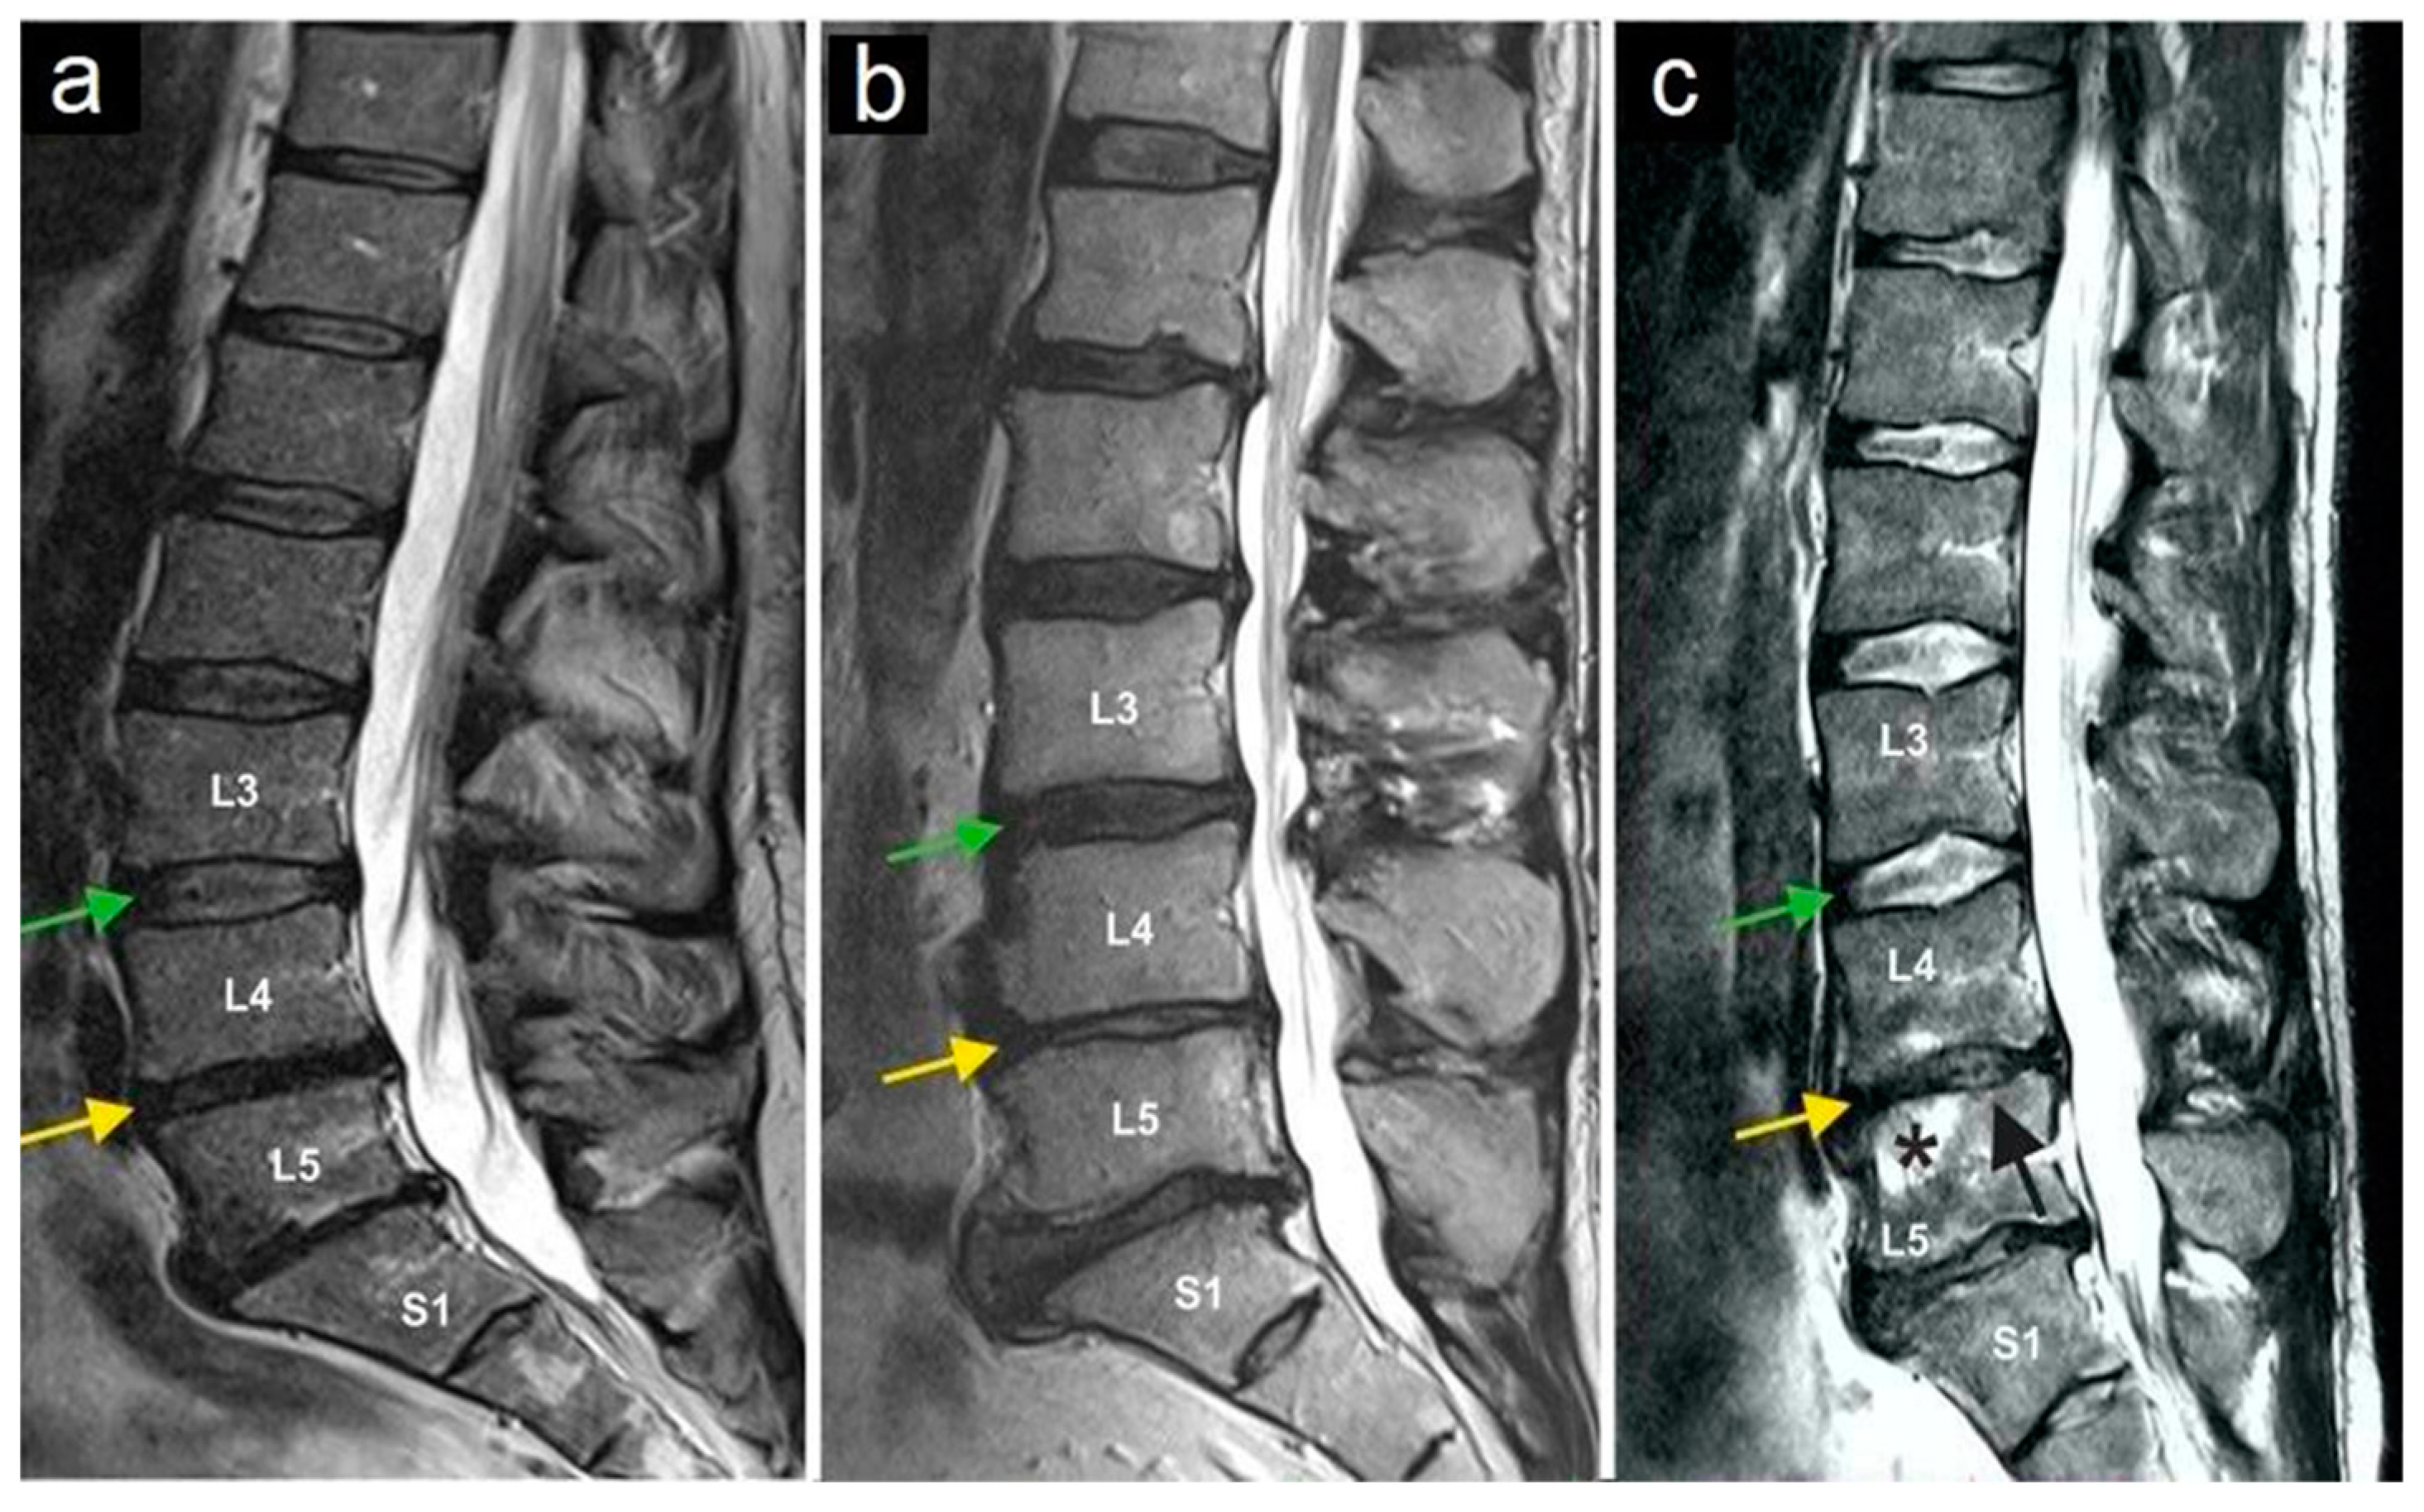

The most common preoperative symptom was local back pain (in 100% of cases). Before treatment, none of the patients had a motor deficit. One patient had suffered from a sensory deficit at L5 on the right side (2.7%) after six previous operations on the lumbar spine. No other neurological symptoms or signs were present during the initial examination. Clinical evaluation showed a compression pain of the facet joints in the affected area during the physical examination in all patients. Only lumbar pain syndromes were included in the evaluation. No one of the study participants suffered from cervical facet joint syndrome. All patients underwent MRI examinations. In the preoperative MRI, nerve root compression, acute fractures, or spondylodiscitis was ruled out in all patients. All patients showed degenerative changes in facet joints of varying degree. In seven patients (18.9%), there were radiological signs of osteochondrosis Modic I and II (Figure 3). Spondylolisthesis was not present in any of the study participants.

Figure 3.

Magnetic resonance imaging of three lumbar spine patients (a–c). The green arrows mark the L3/L4 disc, and the yellow arrows mark the L4/L5 disc. Note the normal structure of the L3/L4 disc, while the yellow arrows indicate a reduced intervertebral disc height (and thus the disc space) at L4/L5, as observed in all three patients. The star (c) marks bone marrow edema in vertebral body L5, and the black arrow (c) indicates the collapse of the superior endplate of the L5 vertebral body.